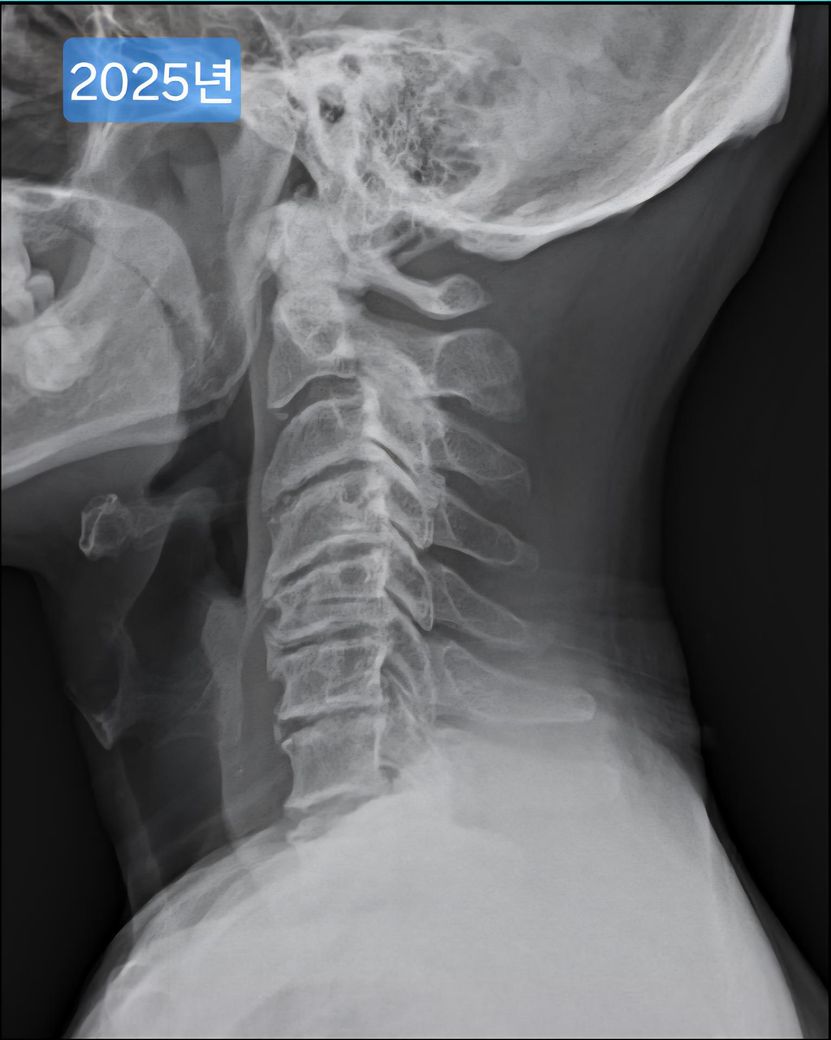

목이 일자목, 경추사이 공간 좁음 등 형태가 안 좋은데요.

여러 방도로 제 목 엑스레이 사진을 보여드리면

현재 목의 형태가 안 좋은건 충분히 알겠는데.

• 1번 째 사진

• 2번 째 사진

• 3번 째 사진

• 4번 째 사진